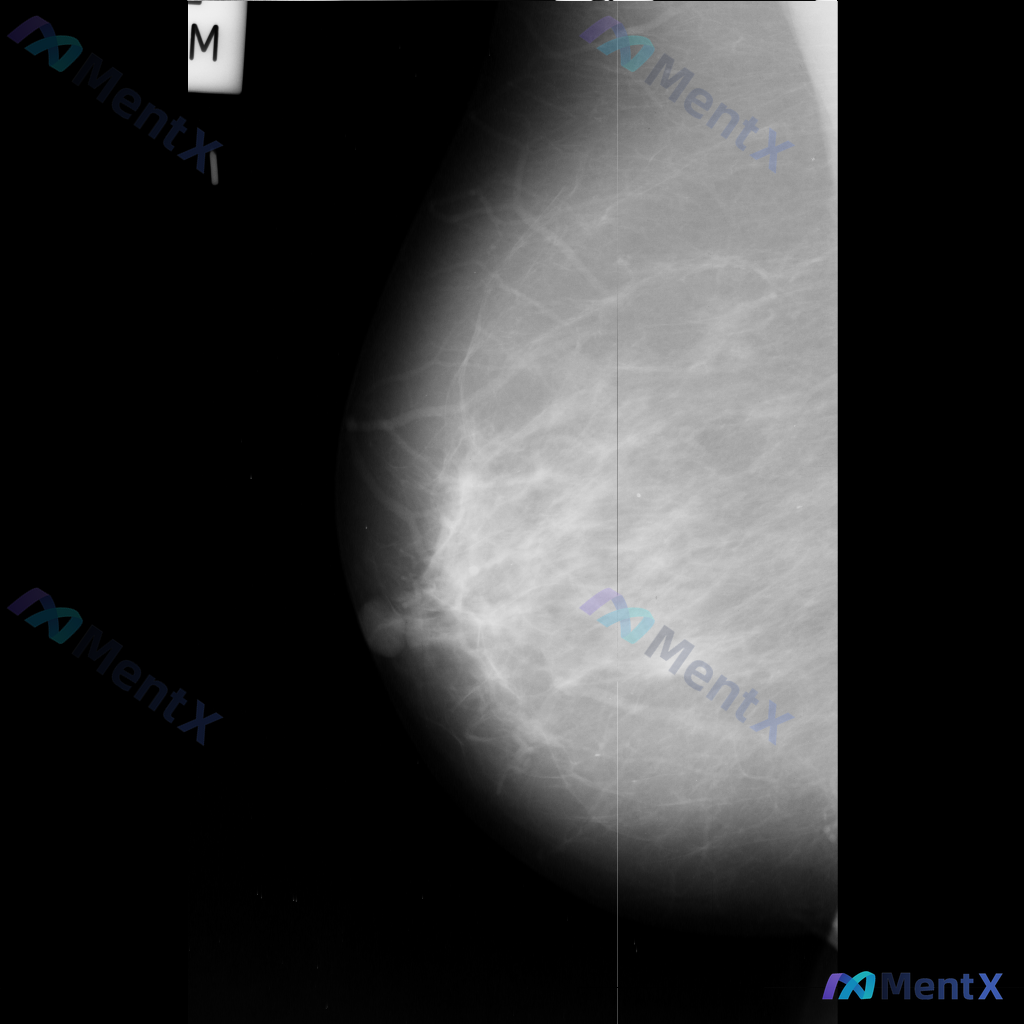

整理到一份乳腺钼靶影像资料,主要异常表现如下: - 部位:乳腺中部偏下方 - 影像征象:局灶性不规则腺体密度增高,伴结构扭曲 - 背景:致密型乳腺 目前仅单张影像资料,未提供其他体位、超声或临床病史。 想和大家讨论一下:单看这组异常表现,你会先往哪个方向考虑?后续如果要进一步明确,你觉得优先做什么检...

整理到一张乳腺钼靶片的读片资料,想和大家讨论下判断方向。 基本情况: - 影像:右侧乳腺内外斜位(MLO)钼靶 - 背景:致密型乳腺(多量腺体型/不均匀致密) 异常表现: 1. 右乳中上象限可见一局限性不对称致密影,形态不规则,边界部分模糊,与周围腺体融合 2. 该区域周围可见可疑结构扭曲,小梁结构...

整理到一张左乳内外斜位(MLO)的钼靶影像资料,先和大家讨论一下读片的情况。 目前已知的信息: - 仅提供了左乳的MLO位单张投照影像 - 影像质量基本良好,基本结构可辨 - 后续补充说明提到患者的乳腺构成类型为不均匀致密型(BI-RADS C) 目前暂时没有更多临床病史、对侧乳腺影像或头足位(CC...

整理到一份乳腺钼靶的影像资料,和大家讨论一下: 目前只有左乳的内外斜位(MLO)视图,提示: - 左乳外侧象限可见一个局限性高密度肿块影 - 肿块形态呈卵圆形,边缘清晰 - 密度高于周围乳腺实质,与周围组织界限明确 - 未见明显结构扭曲、皮肤牵拉或典型恶性钙化等征象 - 乳腺类型为不均匀致密型(BI...